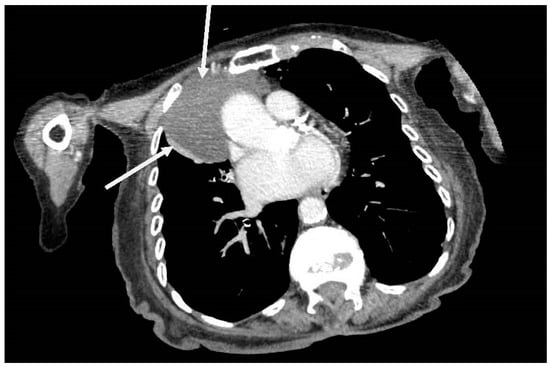

The chest X-ray (CXR) revealed a well-defined hemispherical soft tissue density, projected over the right parahilar region, as shown in Figure 1. No previous CXR was available for comparison. Computerised tomography (CT) of chest, abdomen, and pelvis with contrast demonstrated an 8 cm × 5 cm low attenuation lesion abutting the pericardium, the anterior mediastinum, and anterior chest wall, as shown in Figure 2. The findings were consistent with a large pericardial cyst and no bronchogenic malignancy was identified. Bronchiectatic changes in the middle lobe were consistent with longstanding compression. The patient was treated with intravenous co-amoxiclav and made an uneventful recovery.

Figure 2. Axial computerised tomography (CT) showing an 8 cm × 5 cm low attenuation right sided soft tissue mass arising from pericardium and abutting the anterior mediastinum and anterior chest wall (arrows).